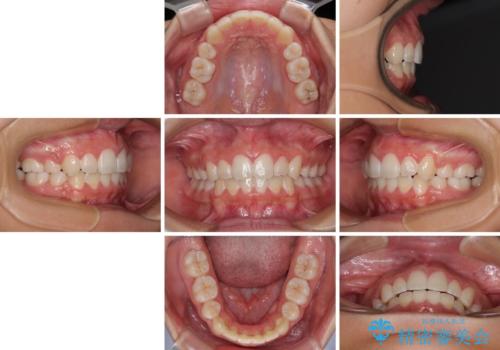

気がつくと唇があいてしまう ワイヤー装置での抜歯矯正

- 口元の突出感で口が閉じにくいとのことで来院された患者様です。

上下左右の第一小臼歯4本を抜歯し、ワイヤー装置での抜歯矯正を行うこととしました。

右側の咬み合わせは、上顎がやや前方位にある状態であったので、通常は補助装置を併用するのですが、高校生ということで補助装置なしで治療を行うこととしました。

口元の突出感が解消され、睡眠時の口呼吸が改善されました。